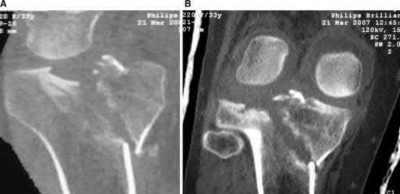

A 25-year-old female is involved in a motor vehicle collision. She presents with the isolated injury seen in Figures A through D. Her leg is swollen but her skin is intact. She has no clinical signs of compartment syndrome. Which of the following treatment options will allow for maintenance of fracture alignment and minimize the risk of soft tissue complications?

The patient presents with a closed distal third metaphyseal-diaphyseal distal tibia fracture with simple intra-articular extension. Immediate intramedullary nailing along with percutaneous fixation of the articular component provides appropriate restoration of length, rotation and alignment and minimizes the risk of wound complication.

Displaced distal third tibia fractures may be associated with simple intraarticular extension. Operative treatment of intra-articular distal tibia fractures has historically been performed with open reduction and internal fixation. Early open reduction and plate fixation of pilon fractures has been associated with high rates of infection and wound complication. In select patterns with simple articular extension, percutaneous screw fixation and medullary nailing may provide appropriate reduction with minimal soft-tissue risk.

Figures A and B demonstrate a distal third tibial shaft fracture with simple intra-articular extension. The axial and coronal CT cuts in Figures C and D further clarify the articular injury. Illustrations A and B demonstrate a comminuted distal third tibial fracture with simple intra-articular extension. Illustrations C and D are fluoroscopic images of the same injury after intramedullary nailing and percutaneous fixation of the articular component.